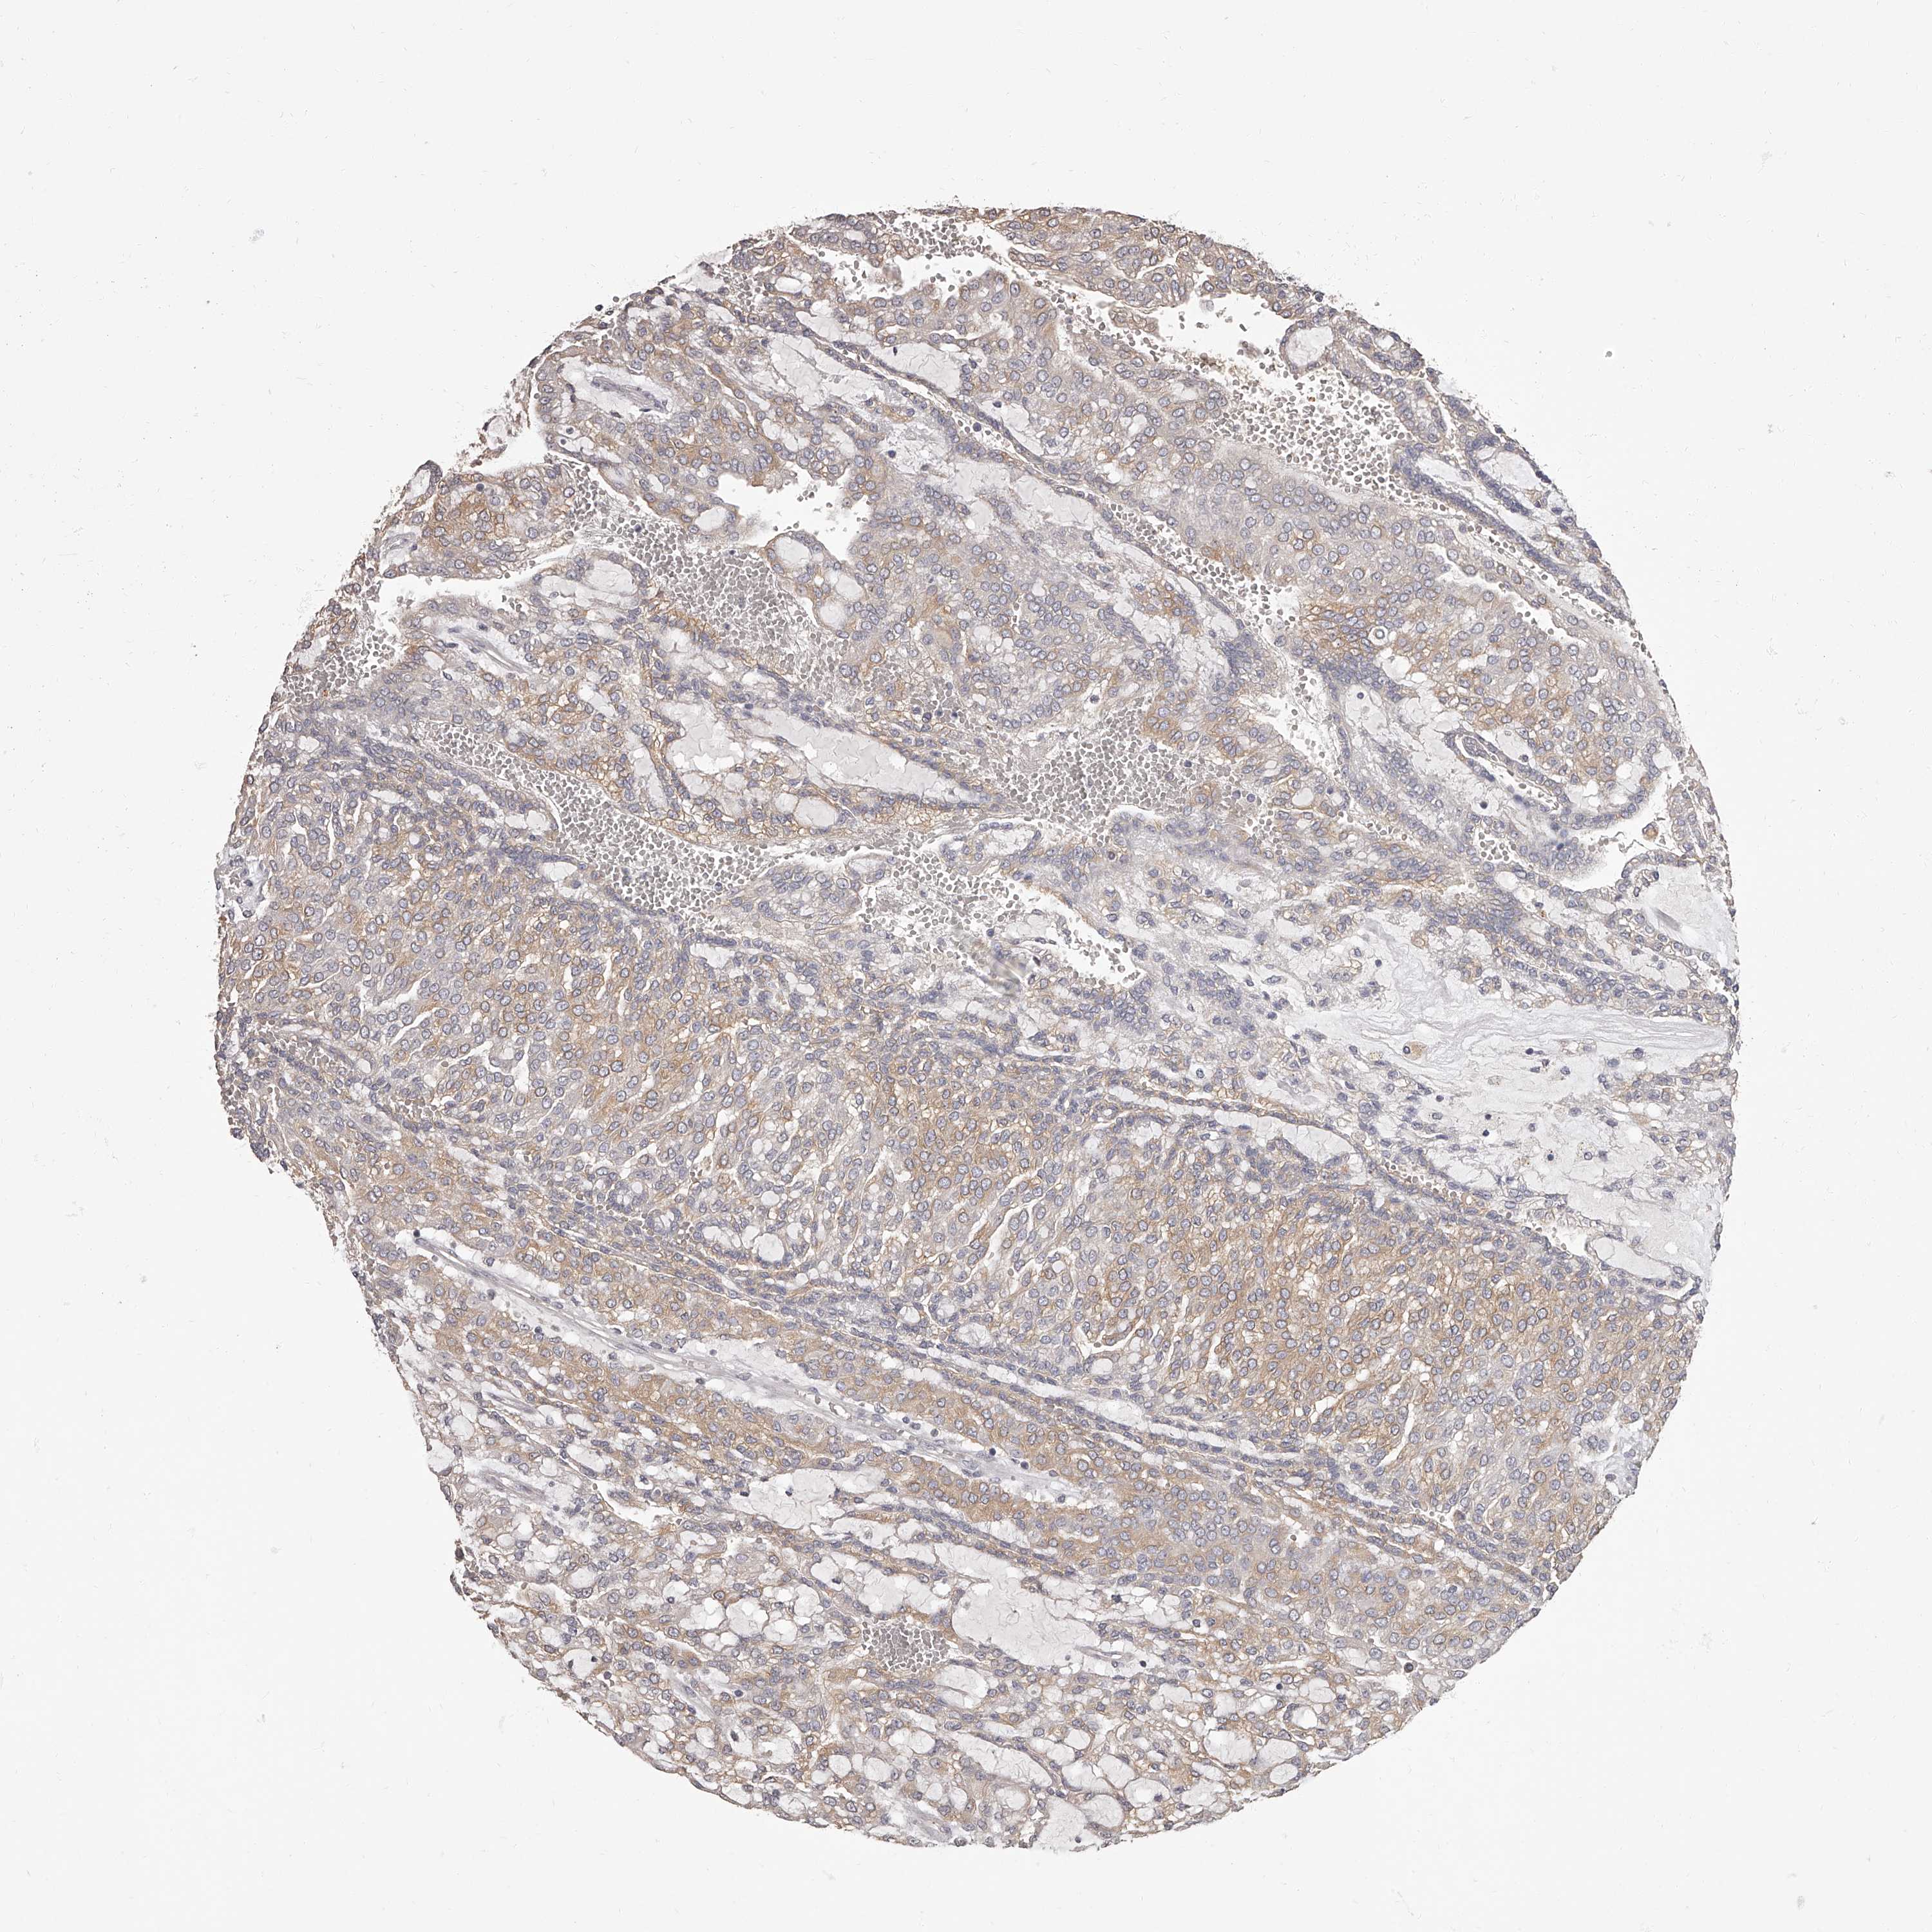

CANCER RENAL CANCER Show tissue menu

KICH TCGA KIRC TCGA KIRC VALIDATION KIRP TCGA PROTEIN RCC CPTAC PROTEIN EXPRESSION